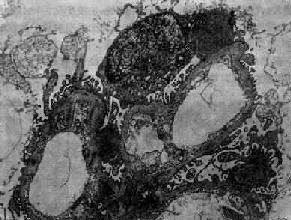

图12-8 毛细血管内增生性肾小球肾炎

电镜下见肾小球毛细血管基底膜表面上皮细胞下有多数驼峰状电子致密沉积物

在电子显微镜下可见肾小球系膜细胞和内皮细胞增生肿胀。基底膜和脏层上皮细胞间有致密物质沉积。这些沉积物大小不等,有的很大,在基底膜表面呈驼峰状或小丘状(图12-8,图12-9)。沉积物表面的上皮细胞足突多消失。基底膜变化不明显有时边缘稍不规则。沉积物一般在发病后几天就可出现,在4~6周内消失。有时基底膜内侧内皮细胞下和系膜内也可见小型沉积物。